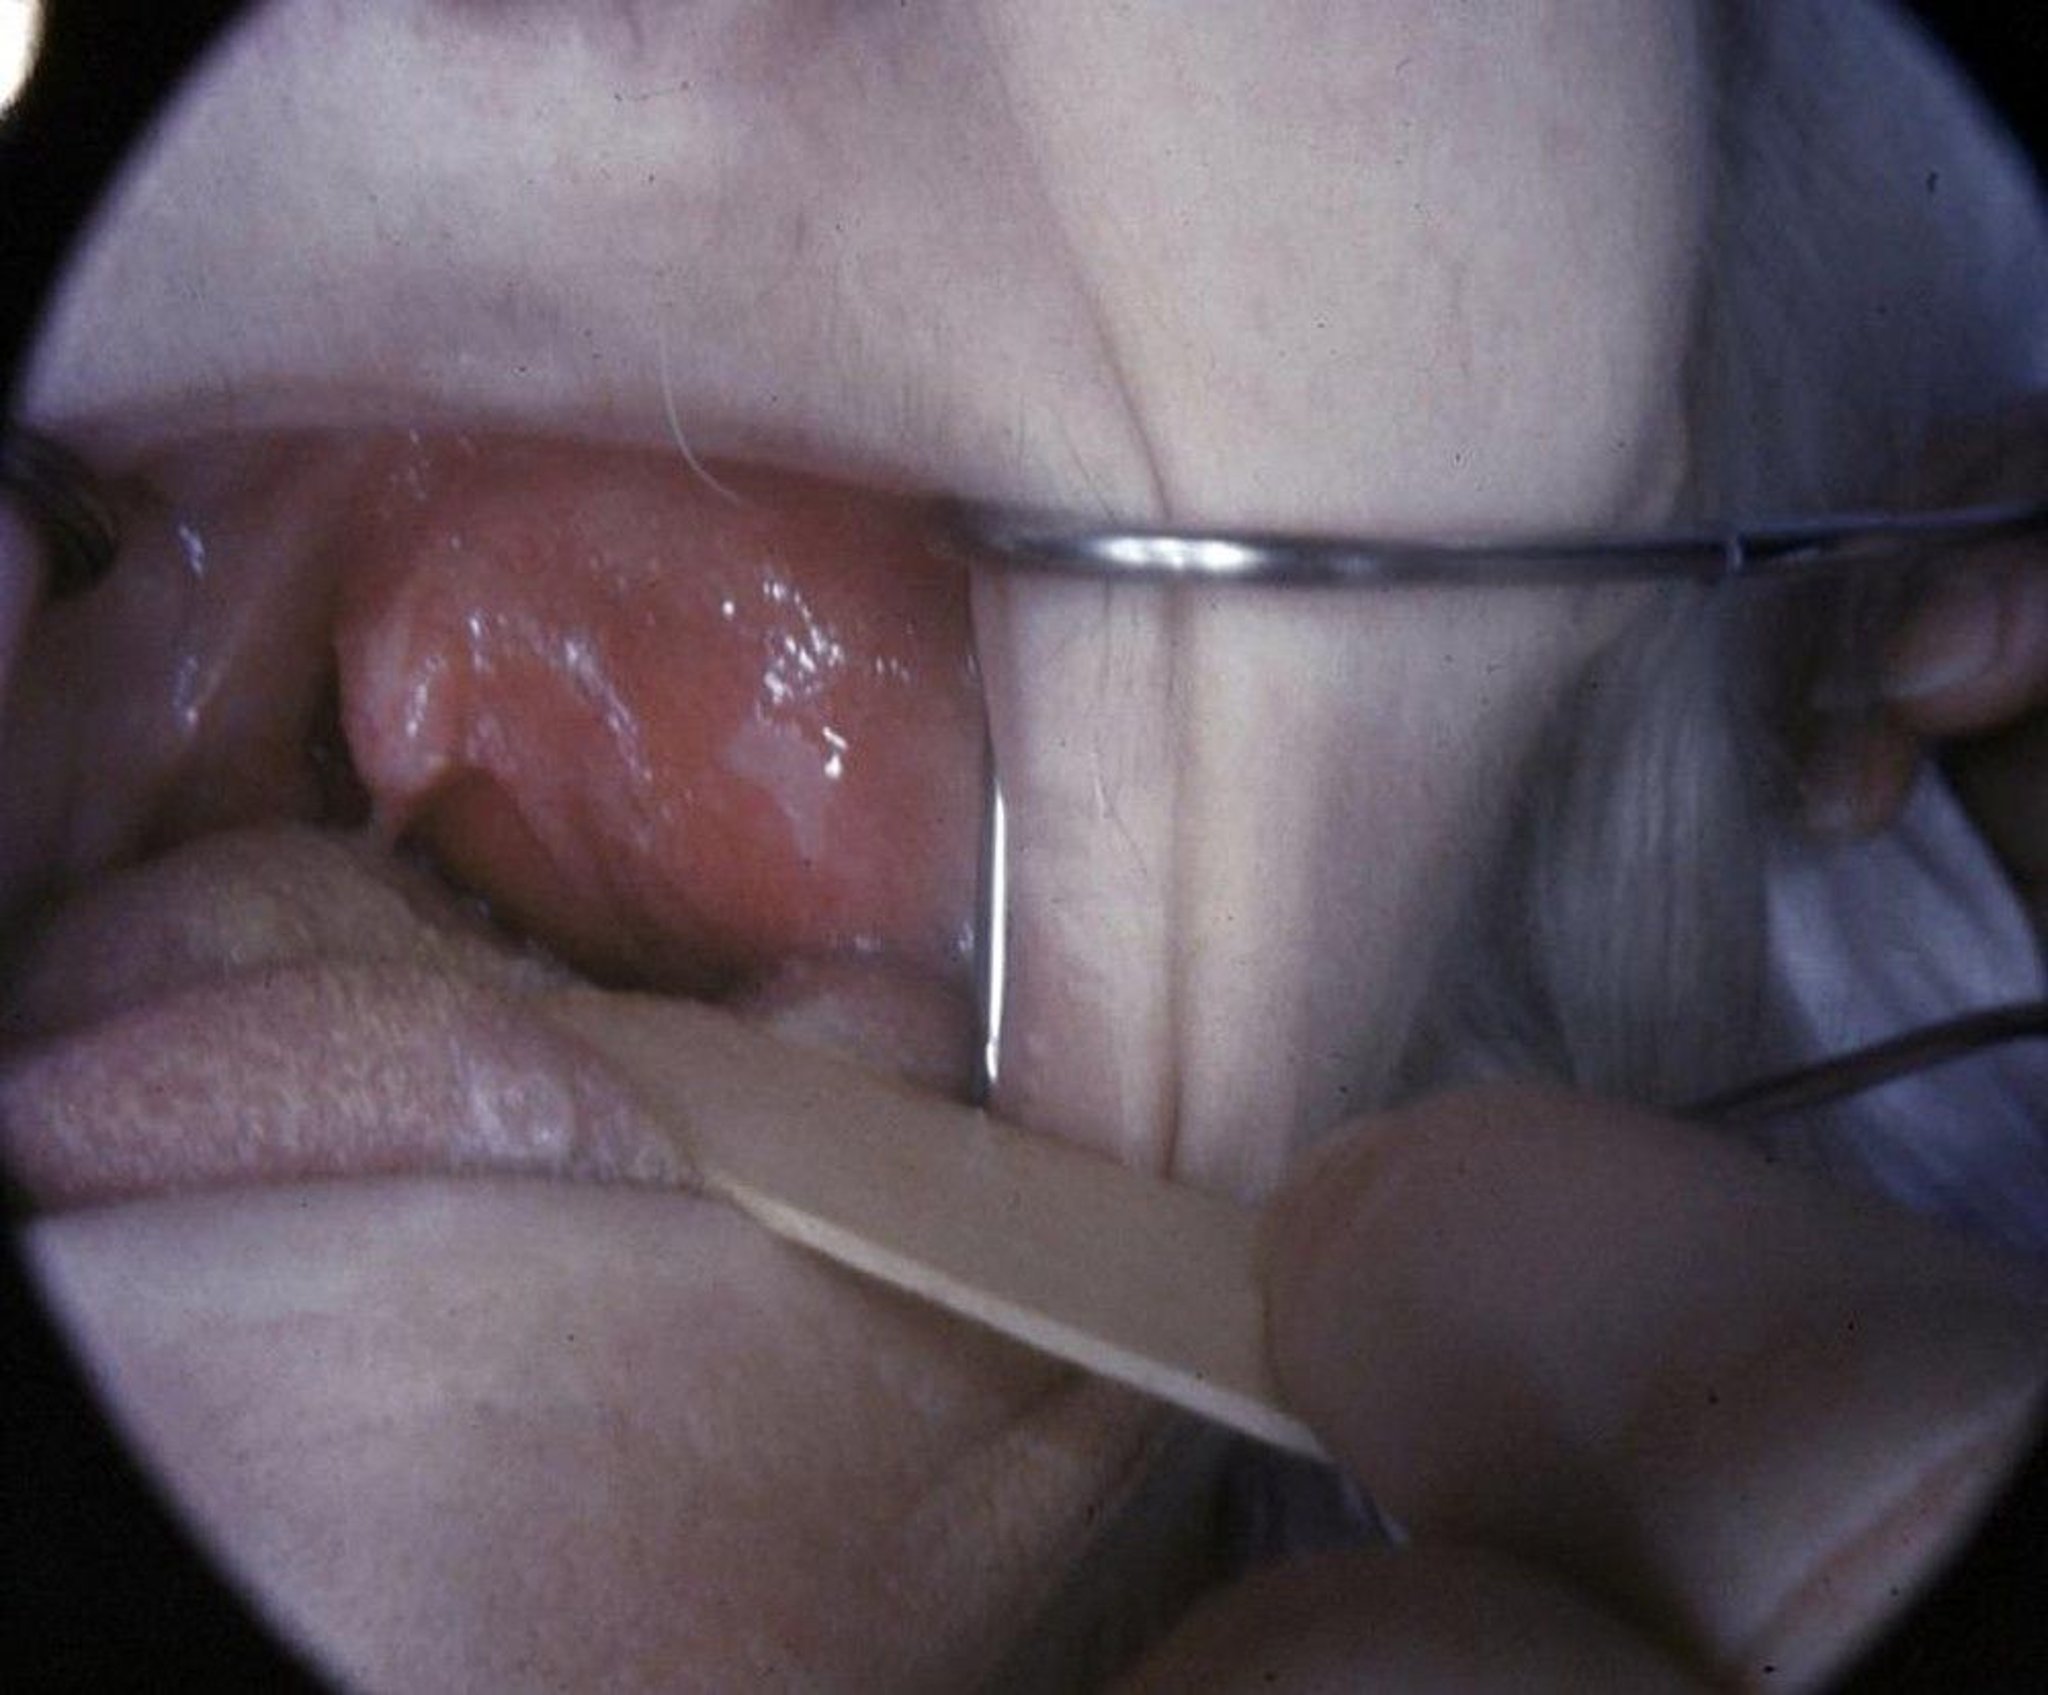

Peritonsillar Abscess

This photo shows peritonsillar abscess with bulging and deviation of the uvula accompanying moderate trismus.

Image provided by Clarence T. Sasaki, MD.